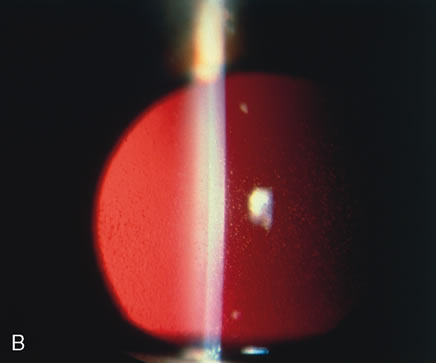

Fig. 25. Meesmann's corneal dystrophy. The characteristic slit lamp appearance is best demonstrated either by retroillumination (A) or through a red reflex (B). The latter best shows the increased distribution of tiny droplet-like lesions in the central cornea.

Histopathologically, numerous tiny intraepithelial cysts are seen, which result from the dissolution of the normal tonofibrillar skeleton of the epithelial cells.126,127 The full thickness of the epithelium is affected, with even the basal cells showing diffuse abnormalities. The matrix of the tonofibrils is composed of an abnormal complex containing a glycoprotein acid mucopolysaccharide compound that contains glycogen. Meesmann's corneal dystrophy is caused by mutations in the genes for cornea-specific cytokeratins K3 or K12.128,129